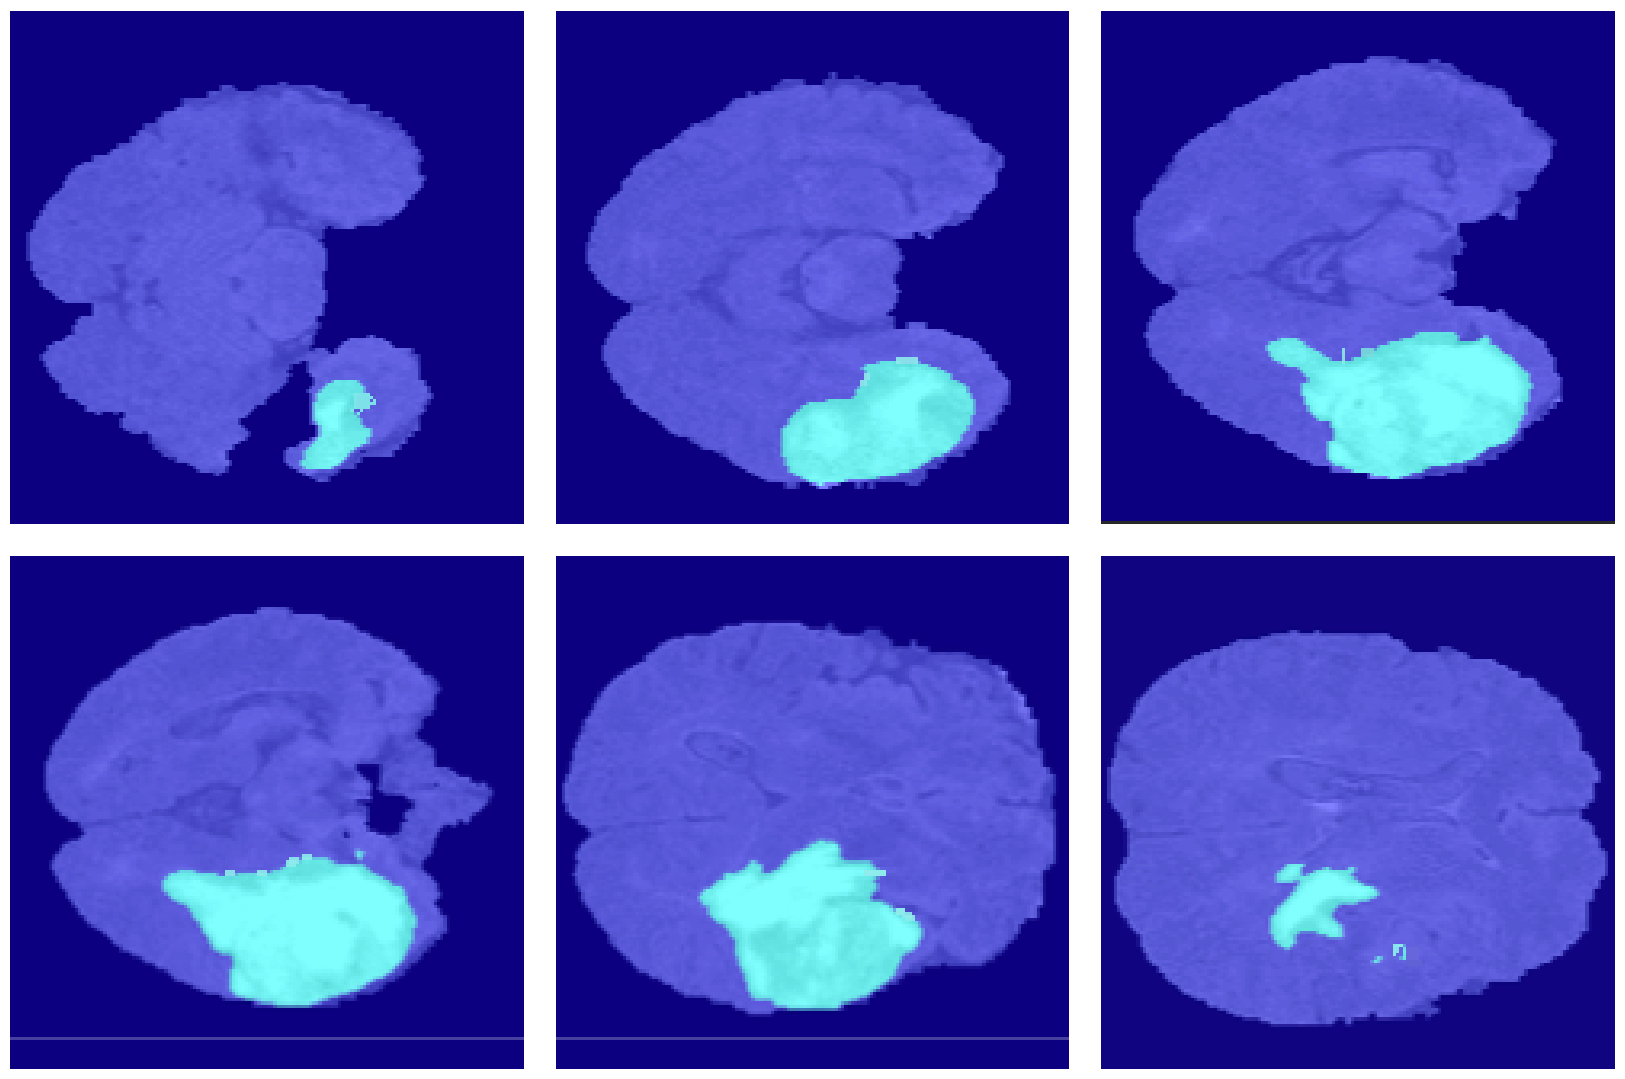

4.2. Segmentation Results